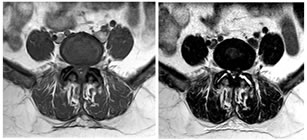

CASE 2

T1 AND T2 W AXIAL IMAGES SHOWING DIFFUSE DISC BULGE WITH SEVERE BILATERAL FACETAL ARTHROPATHY AND LIGAMENTA FLAVA THICKENING AT L5-S1 LEVEL CAUSING MODERATE THECAL SAC STENOSIS, NARROWING OF LATERAL RECESS WITH COMPRESSION OVER BILATERAL TRAVERSING NERVE ROOTS. AN INTRASPINAL SYNOVIAL CYST IS ALSO SEEN ARISING FROM FACET JOINT ON THE RIGHT.

AXIAL T1 AND T2 W IMAGES SHOWING HYPOINTENSE SIGNAL ON PEDICLE OF S1 VERTEBRA ON LEFT SIDE SUGGESTIVE OF SCLEROTIC LESION POSSIBLY OSTEOMA